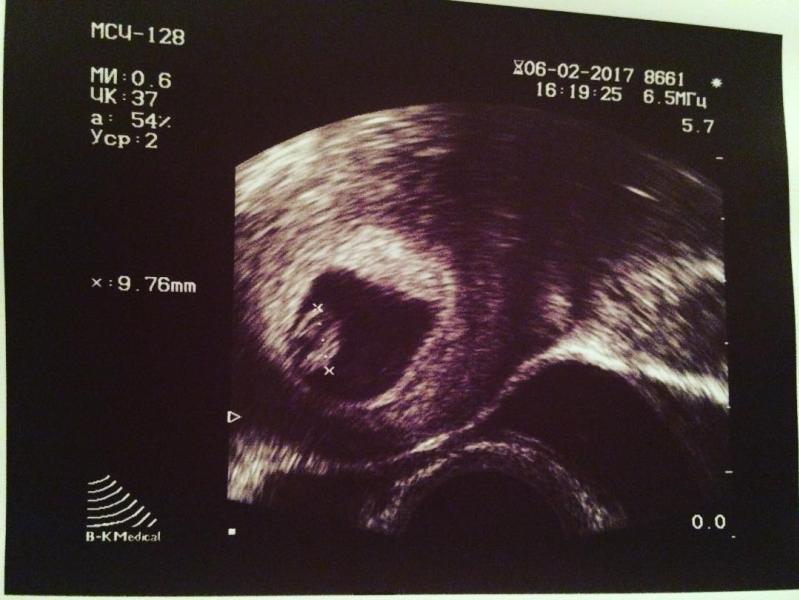

Привет вам , мои дорогие ! 6 февраля состоялось мое первое УЗИ и первый приём к гинекологу.

Я слышала как бьется сердечко моей крохи❤️, не сдержалась и пустила слезу .

У нас 7 недель . Через день 8😍 #беременная #беременяшка #вожиданиичуда #вожидании #узималыша #узи #скоромама #маленький #маленькийвживотике #пузожитель